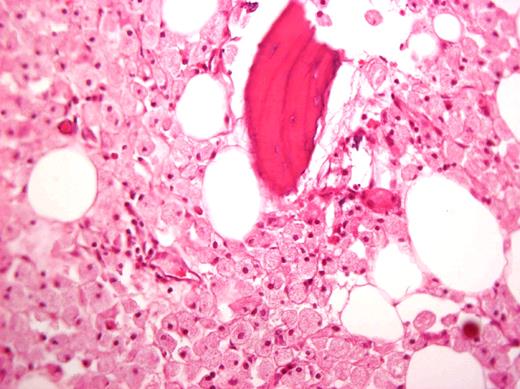

In the past, large joint replacement was not offered in GD because of concern of introducing prostheses into a compromised milieu. This bias has been proven to be wrong, and patients with GD should be candidates for arthroplasty on the basis of criteria of pain and poor function just like others.38-43 Moreover, orthopedic surgery is still a mainstay of GD management for patients who have developed irreversible joint damage before ERT and patients with skeletal complications despite ERT.43 I recommend a team approach before surgery particularly for patients with bleeding tendencies. Interestingly, Gaucher cells in the femoral head are often seen despite long-term ERT (Figure 3).44,45

Histologic specimen from a femoral head removed during arthroplasty of a patient after 15 years of ERT. Courtesy of Dr Ehud Lebel, Shaare Zedek Medical Center, Jerusalem, Israel.